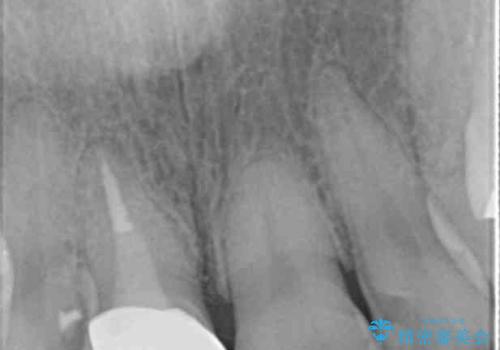

折れてしまった前歯 オールセラミックによる審美改善

- 「野菜をかじった際に前歯がぐらつき、その場で取れてしまった。前歯を入れたい。」と希望され来院されました。

残っている歯質(歯の量)は非常に少ないものの、歯を抜かずに残したい希望が強く、また破折リスクが高いことも

ご理解いただいた上で歯を残しセラミック治療を計画します。

破折リスクを少なくするため前歯でかじったり硬いものを噛み切る等の行為は避けた方が良いとお伝えし、現状5年問題なく経過しています。